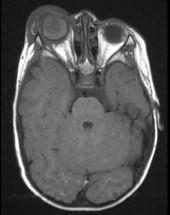

问题 以下关于视网膜母细胞瘤(如图)描述错误的是 ( )

选项 A、90%发生于3岁以前 B、男性多于女性 C、可出现钙化灶 D、是儿童最常见的原发性眼内恶性肿瘤 E、双眼发病约占30%~35%

答案 B